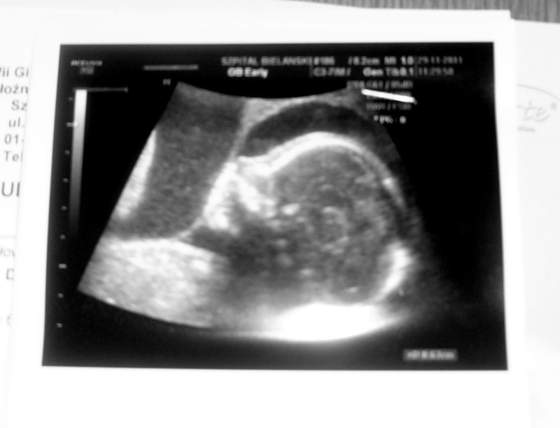

Teraz przedstawię Wam niusie.Przepraszam za jakość.img2057po.jpg

img2058vz.jpgTu mamy Jasia.